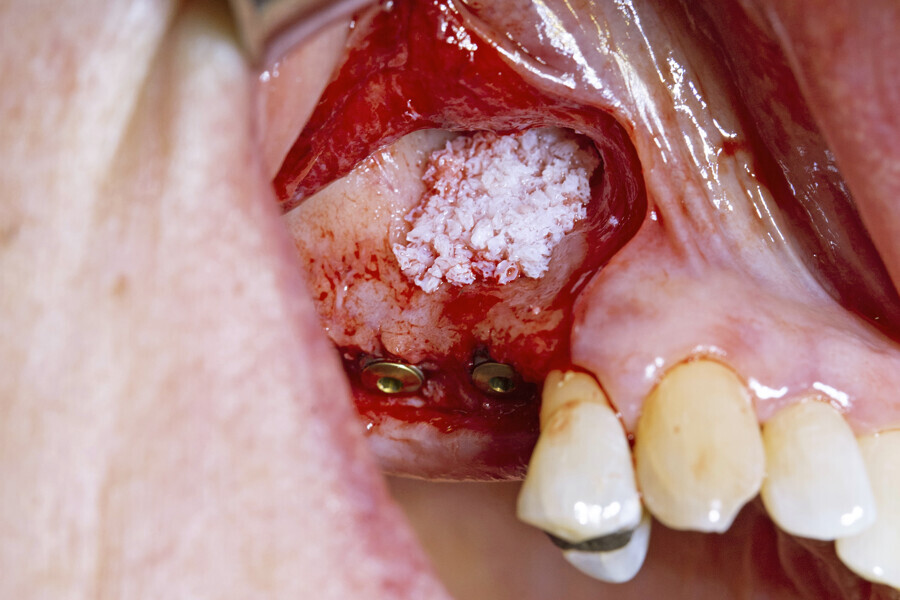

Next, the large quantity of autogenous bone collected with the disposable BoneTrap (Dentsply Sirona) during surgery was used to augment the small bone fenestration (Figs. 6 & 7), and Symbios Xenograft Granules were layered over the autogenous bone (Fig. 8). Finally, Symbios Collagen Membrane SR (15 × 20 mm) was trimmed to shape to complete the guided bone regeneration procedure (Fig. 9). The wound was closed with PGA sutures (Fig. 10), and radiographic evaluation was performed to verify the implants postoperatively (Fig. 11). Three months later, medium Healing Abutments EV were placed (Fig. 12).

Fig. 8: Symbios Xenograft Granules layered over the autogenous bone.